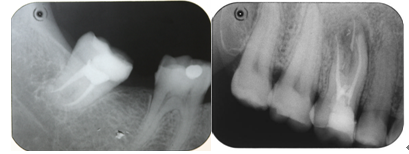

牙龈长脓包说明牙周发炎了,如果是牙根部位的牙龈肿了大包,说明是根尖部位发炎了,这对牙齿的影响比较大,不仅牙痛还会牙齿松动。以前遇到这种情况牙医都是建议拔牙的,无法保留。牙根边的牙龈上长了个脓包是怎么回事呢?怎么引起的?一般是对应的牙根发炎了,临床上称为慢性根尖炎。牙根长期炎症破坏牙槽骨,形成从根尖到牙龈的瘘管,炎症产生的分泌物便由此流出,“脓包”就是瘘管口。>>点击在线咨询详情<<

根尖炎很多情况是龋齿没有得到及时的治疗,引发牙髓感染,导致最后的根尖周病变,才产生根尖囊肿。根尖囊肿一定要及时医治,否则情况恶化会演变为骨髓炎。需要拍片、做根管治疗。>>点击在线咨询详情<<